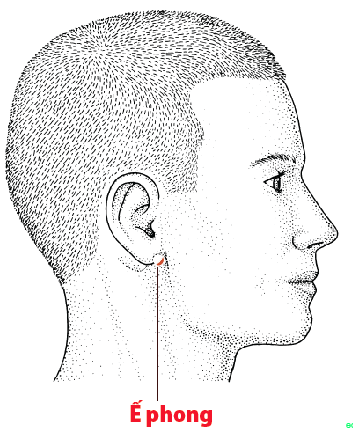

5. Huyệt Ế Phong: Đây là huyệt thường được sử dụng khi triệu chứng ù tai là biểu hiện chính, cảm giác tai như bị bít kín hoặc nghe âm thanh vang trong tai.

– Vị trí: Nằm ngay sau dái tai, trong hõm nhỏ giữa xương hàm dưới và xương chũm. Khi há miệng nhẹ, hõm này sẽ rõ hơn.

– Tác dụng: Giúp hỗ trợ lưu thông khí huyết quanh vùng tai, từ đó cải thiện cảm giác ù tai và nặng tai.

– Cách thực hiện: Day ấn nhẹ bằng đầu ngón tay trong 1–2 phút mỗi bên; nên thực hiện vào buổi sáng sau khi thức dậy hoặc ngay khi cảm thấy tai bắt đầu ù.

Vị trí huyệt Ế Phong.